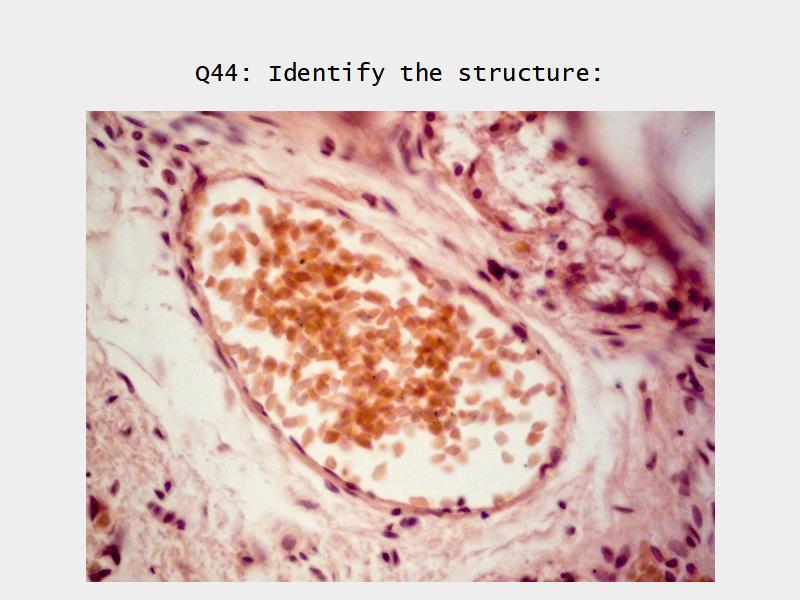

The cardiovascular system needs to be connected to the respiratory system.Path of O2 and CO2

- List complete

- With layers

- And cells

- And function of each

Components of the Blood-Air Barrier?